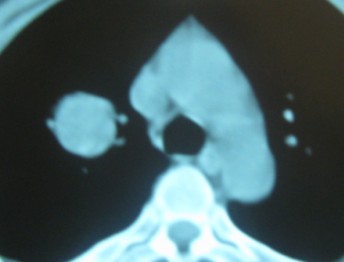

右肺上叶良性肿瘤---错构瘤/硬化性血管瘤/炎性假瘤等。

考虑血管源性肿瘤,硬化性血管瘤可能性大;

不除外错构瘤。

考虑右肺上叶良性肿瘤(硬化性血管瘤?炎性假瘤?)。